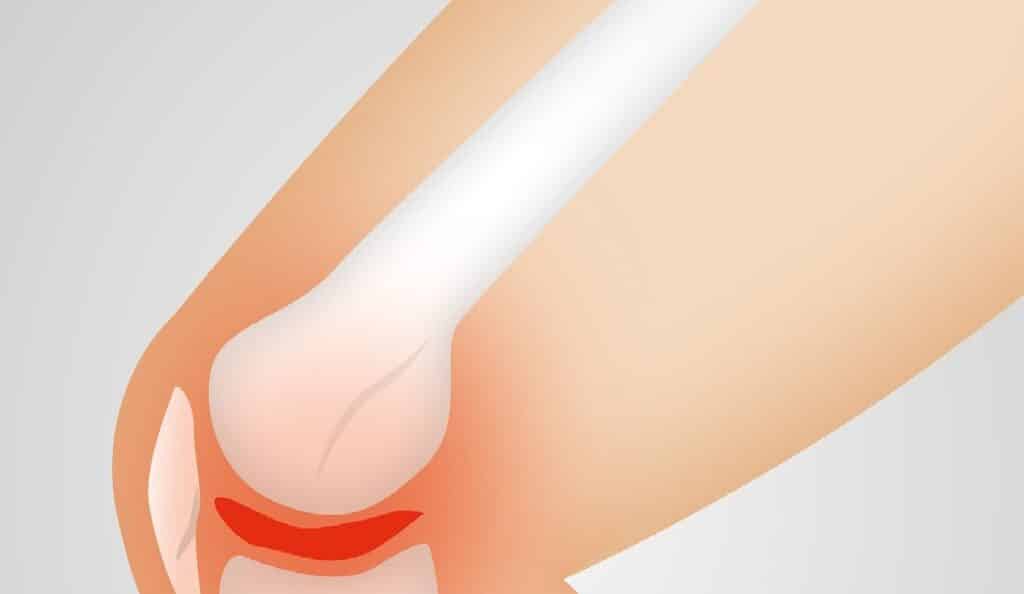

Arthrosis: Symptoms and Tests to Perform

Arthrosis and its symptoms. How to determine if joint problems are due to arthrosis or other causes? At Nefrocenter Diagnostica, you can undergo all tests to assess the health of your joints. This way, if arthrosis is diagnosed, the correct therapy can be planned to prevent the condition from worsening. Arthrosis typically appears after age […]